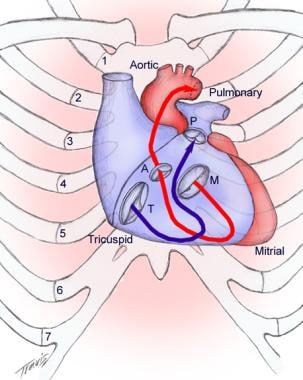

B the relevant anatomy shown from the front view. The tricuspid valve lies between the right atrium and the right ventricle and is placed in a more apical position than the mitral valve. The tricuspid valve has an area of 4 to 6 cm square and is located between the right atrium and the right ventricle of the heart.

The valve has anterior posterior and septal leaflets cusps the bases of which attached around the av orifice to the fibrous ring fibrous skeleton of the heart. Blood collects within the right atrium and it must flow through the tricuspid valve in order to enter the right ventricle. The tricuspid valve functions as a one way valve that closes during ventricular systole to prevent regurgitation of blood from the right ventricle back into the right atrium.

In normal heart the tricuspid valve is located slightly closer to the apex than the mitral valve. The red dotted lines show the direction of dilation of various structures in the setting of secondary tricuspid regurgitation. Unlike the aortic and mitral valve it is not possible to visualize all tv leaflets simultaneously in one cross sectional view by standard two dimensional echocardiography 2de either transthoracic or transesophageal due to the position of tv in the far field.